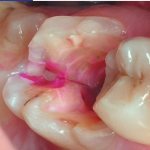

• pulpitis and caries;

Painful sensations may appear due to the root of the tooth affected by pulpitis or caries. The reason for this may be dental treatment, which resulted in inflammation of the gums. It may also be associated with canal injury and poor filling.